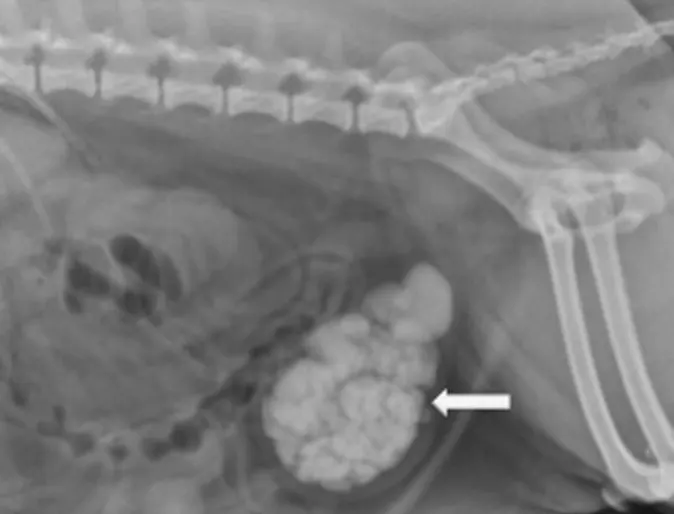

Abdominal radiographs (x-rays) are the most definitive diagnostic tool for detection of most uroliths (figure 4 + 5A).

Figure 4. Radiograph (x-ray) of a canine bladder with multiple uroliths. Photo courtesy of Dr. Joanne Franks, Dallas Veterinary Surgical Center.